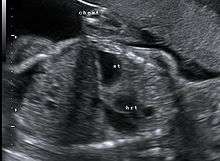

This condition can often be diagnosed before birth and fetal intervention can sometimes help, depending on the severity of the condition.[5] Infants born with diaphragmatic hernia experience respiratory failure due to both pulmonary hypertension and pulmonary hypoplasia. The first condition is a restriction of blood flow through the lungs thought to be caused by defects in the lung. Pulmonary hypoplasia or decreased lung volume is directly related to the abdominal organs presence in the chest cavity which causes the lungs to be severely undersized, especially on the side of the hernia.

Survival rates for infants with this condition vary, but have generally been increasing through advances in neonatal medicine. Work has been done to correlate survival rates to ultrasound measurements of the lung volume as compared to the baby's head circumference. This figure known as the lung to head ratio (LHR).